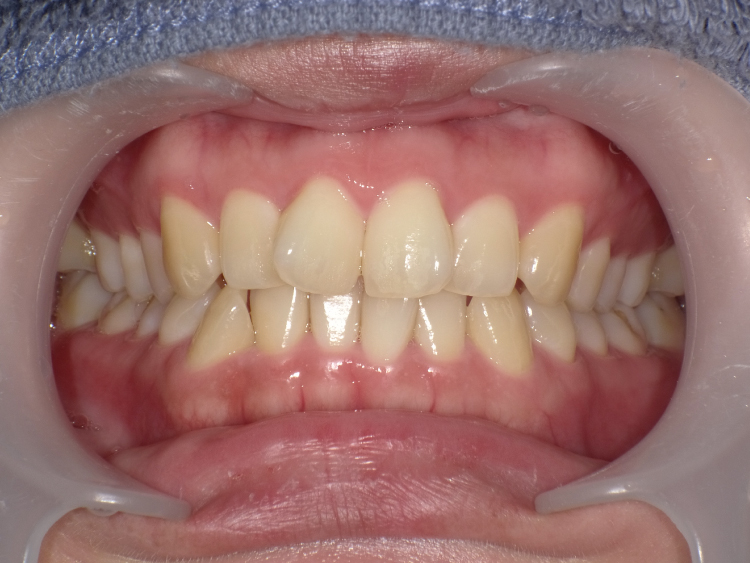

症例4

治療前

治療後

| 主訴 | 右上1番出ている 上のみ部分矯正希望 |

|---|---|

| 治療 期間 |

約8ヶ月 |

| 治療費 | 220,000円(税込)/調整費用別途 |

| 治療 内容 |

上の前歯部にワイヤーを着けて進めていく、プチ矯正で施術。 |

| 治療の リスク |

奥歯を動かさないので、前に出して並べていく。 歯と歯が移動するスペースを作るので、知覚過敏の症状がまれにでる。 装置による清掃の難しさから、歯肉炎や歯周病、虫歯の進行がするリスクが高まる。 歯を動かすことで、歯茎が下がるリスクある。 矯正終了後は、リテーナーを使用し、後戻りを防ぐ必要がある。 |